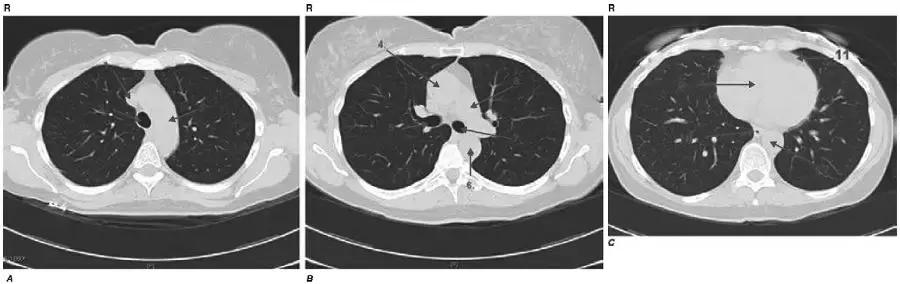

图4-2 正常的胸部断层

1.上腔静脉;2.气管;3.主动脉弓;4.升主动脉;5.右主支气管;6.降主动脉;7.左主支气管;8.主肺动脉;9.心脏;10.食管;11.心包膜;12.降主动脉